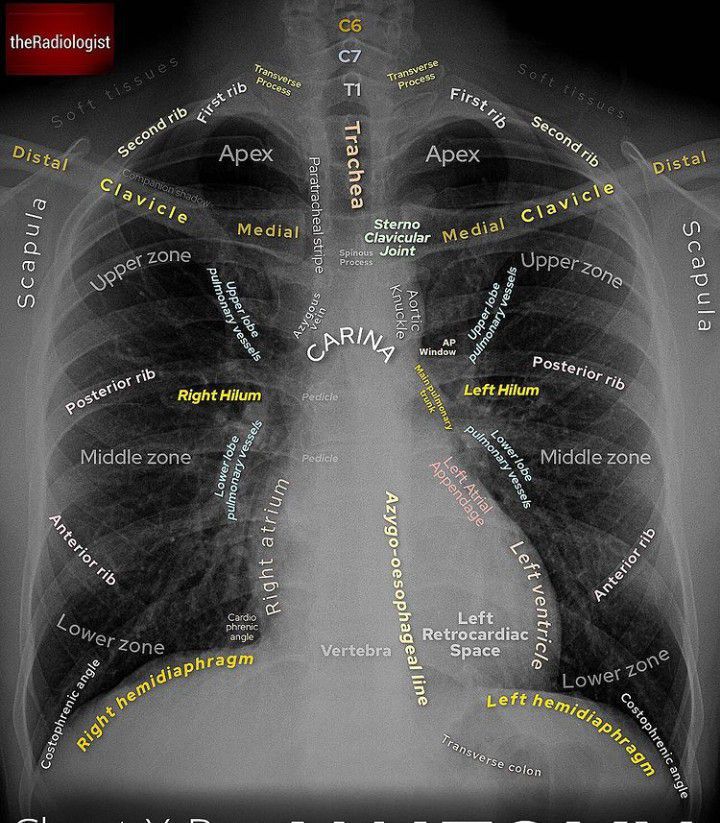

Anatomy of Chest Xray

The attached image highlights the features of chest radiograph. Image via: https://www.instagram.com/p/CWi0U9isZ7Q/?utm_medium=copy_link